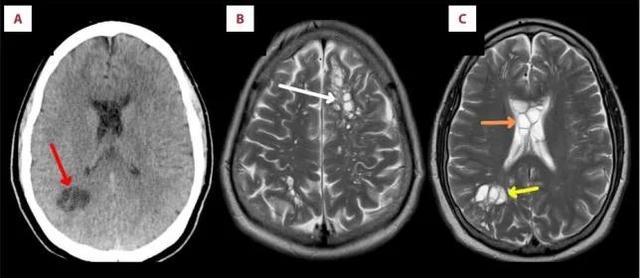

经电脑断层与磁力共振扫瞄造影检查后发现,该男子的左右脑都有多个囊肿,并伴随出现肿胀情况,其后确认他的脑部寄生的是猪肉绦虫(pork tapeworm),甚至在脑内产卵。

▲患者的脑部被寄生虫入侵,引致囊肿。图片来源:《美国期刊病例报告》